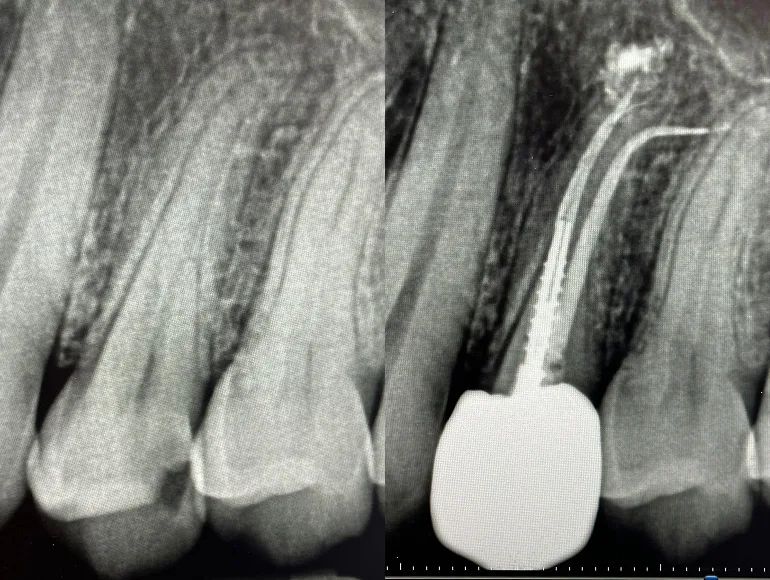

Retreatment of Rootcanal

Case by Dr. Taha Azimaie: Retreatment of failed rootcanal can give a patient another chance to retain the tooth. Retreatment is case selective and not all failed rootcanals are treatable. In this case root canal has failed due to poor sealing of the canals (The white lines in the roots) during the first treatment. Please note the sharp deviation of the canal at the tip of the root (the white line)